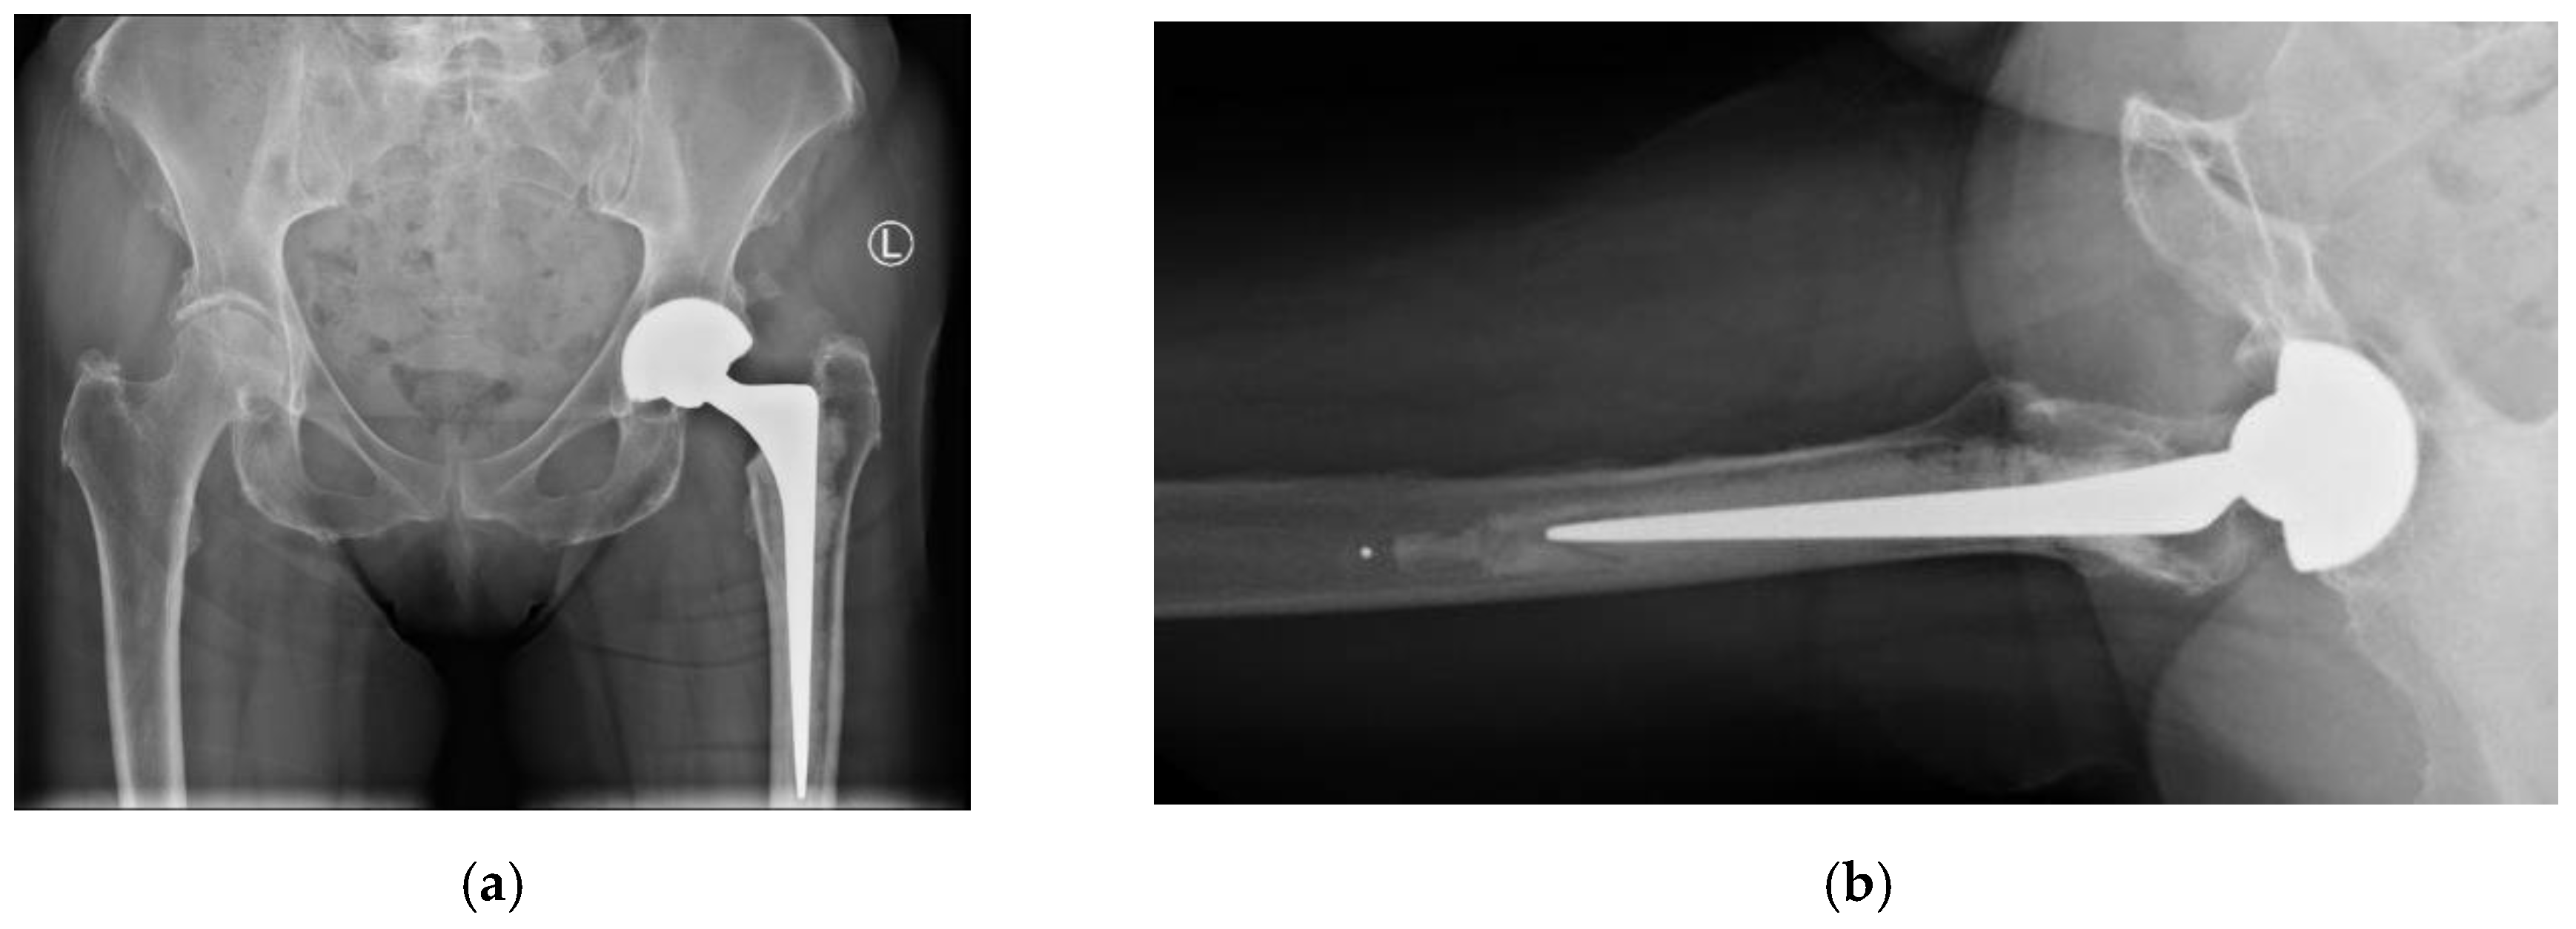

Overall, at one-year follow-up there was no case of dislocation (0.0 %), demonstrating excellent stability. All radiographs demonstrated appropriate component positioning and no radiographic loosening (AP/lateral views) of the implant.

Figure 1. Postoperative radiographs at 1 year follow-up. ​1a) AP view showing cemented CPT stem and neutral cup positioning (Left). ​1b) Lateral view confirming absence of radiolucency around the acetabular component.

Early complications (≤6 weeks) were primarily medical (6.6% Anaemia, 4.2% VTE), rather than implant related. There was one case of PPF (0.8%), which resulted in the revision of the acetabulum. There are no dislocations or early mechanical failures identified at this phase. All radiographs post-operative demonstrated appropriate component positioning and no radiographic loosening (AP/lateral views) of the implant.

The incidences of other surgical complications were low (2.5% superficial infection and 0.83% deep infection). There was also no deep infection in the 30-day postoperative window - an indication of stringent antiseptic protocols and appropriate antibiotic prophylaxis. Other complication rates in our series were low, and importantly we recorded no intra-prosthetic dissociations of the dual mobility liner - a rare complication unique to these implants (typically <1% in literatures [25]). All radiographs (postoperative and at 1-year follow-up) demonstrated appropriate component positioning and no radiographic loosening (AP/lateral views) of the implant. These findings further indicate the robustness of the surgical and institutional protocols.